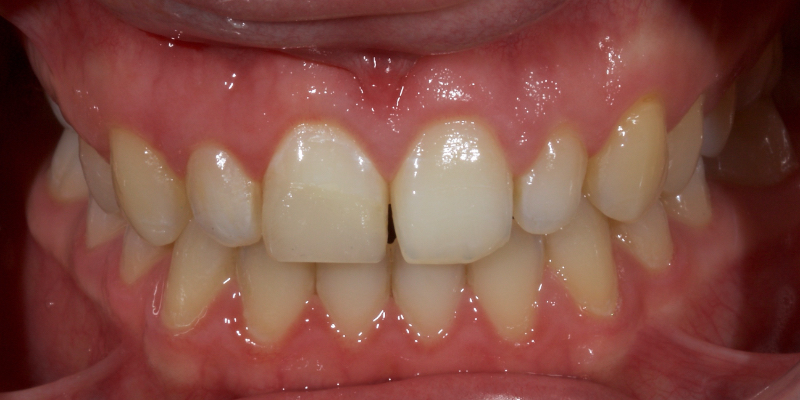

Historically, discolored anterior teeth were treated with indirect ceramic restorations, such as crowns or veneers. This can be illustrated in the case shown in Figure 1, where the discolored left central incisor (2.1), along with two other incisors, was treated with lithium disilicate ceramic veneers (Fig. 2). More recently, direct composite materials that incorporate specialized “opaquers” have also been utilized for treatment.

This article explores a more modern, minimally invasive approach to discolored non-vital teeth using the “modified walking bleach” approach. Figure 3 (before treatment) and Figure 4 (after treatment) show an example of this highly conservative approach.